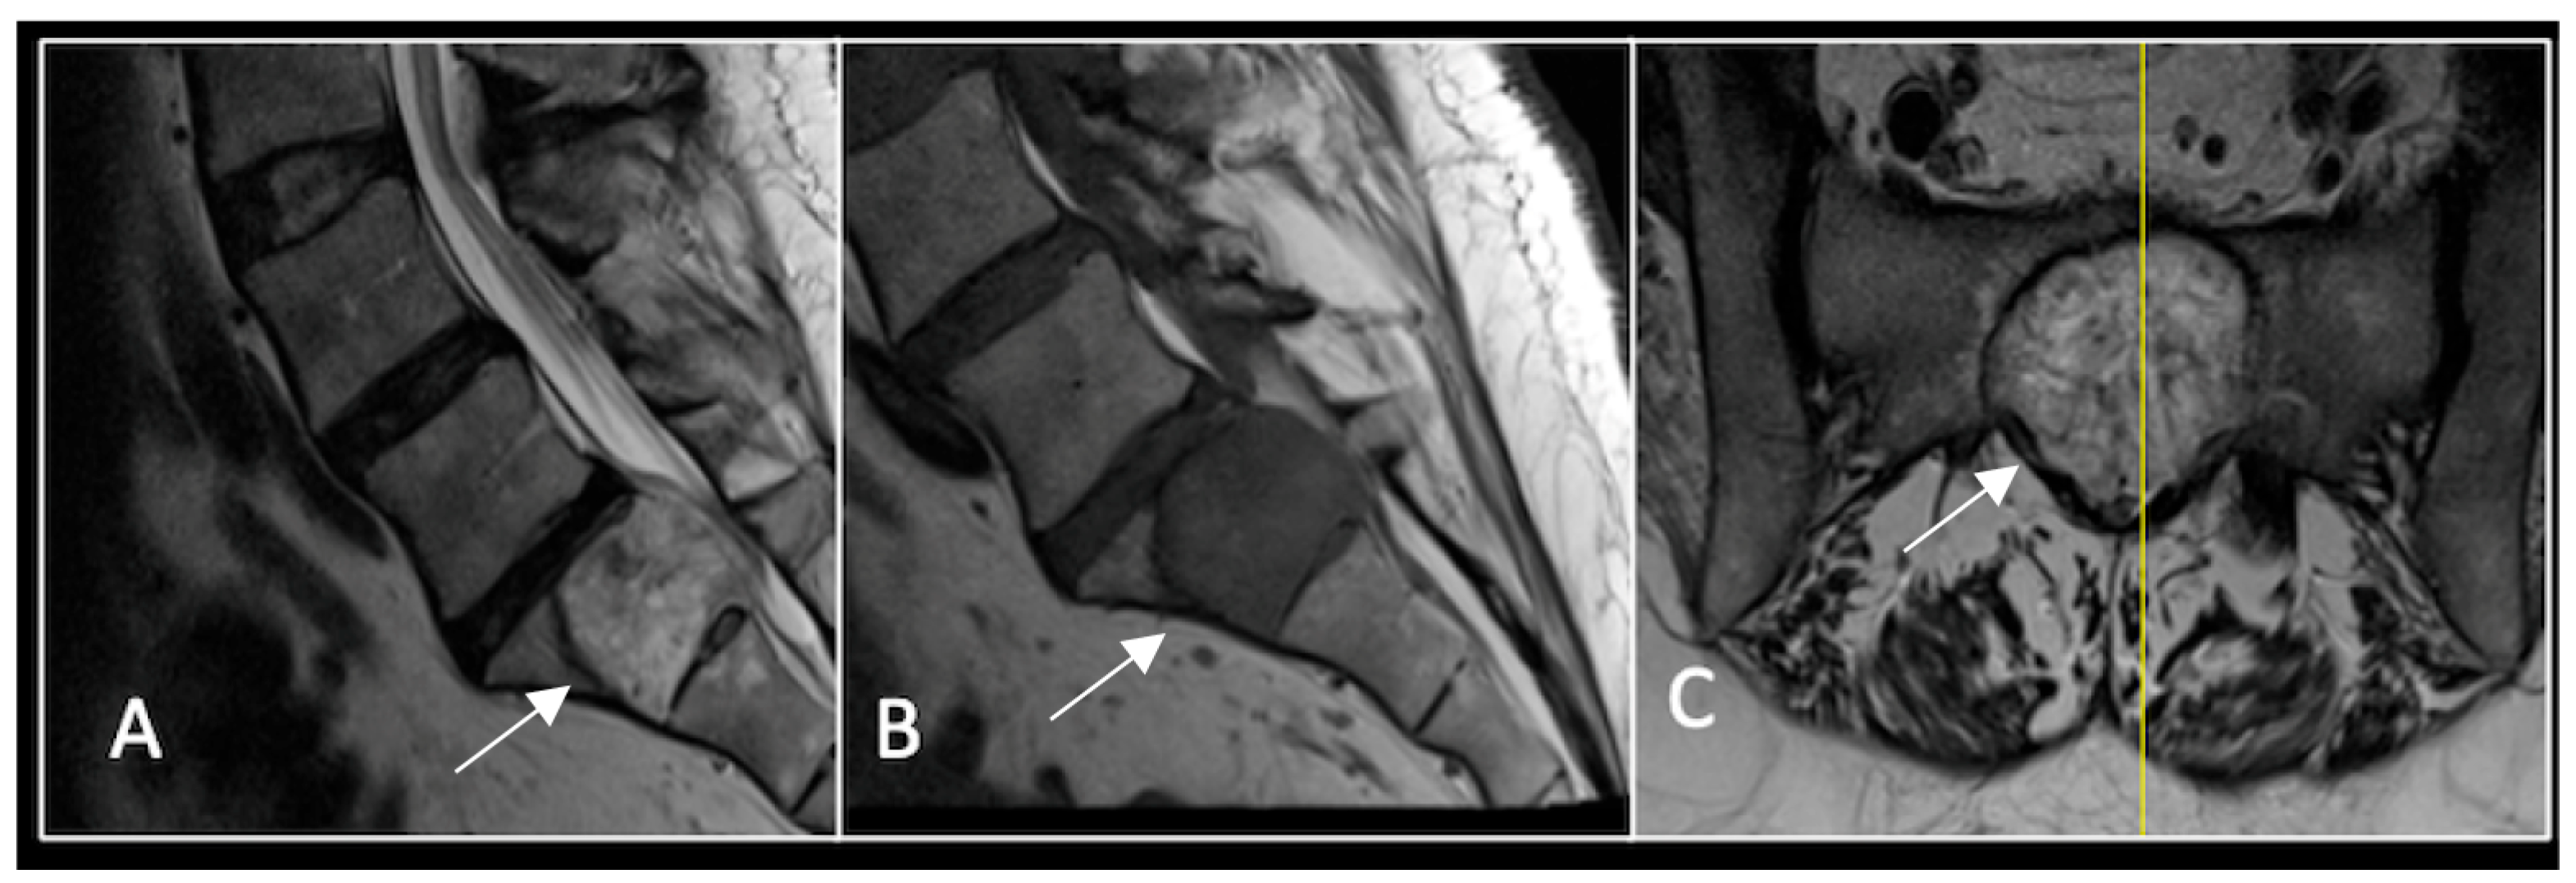

Figure 7.

The MRI demonstrates a left-sided lobular mass (arrow) with invasion of the C2/3 vertebral body and epidural extension, but no cord compression. The yellow line on the axial image indicates the axial slice level. (A) T2W sagittal; (B) T1W sagittal; (C) T2W axial.

Figure 8.

MRI demonstrating a left-sided posterior approach to the cervical spine with significant reduction in residual gross tumour volume (arrow) and circumferential decompression of the spinal cord. The yellow line on the sagittal images denotes the level corresponding to the axial section. (A) T2-weighted sagittal; (B) T1-weighted sagittal; (C) T2-weighted axial.